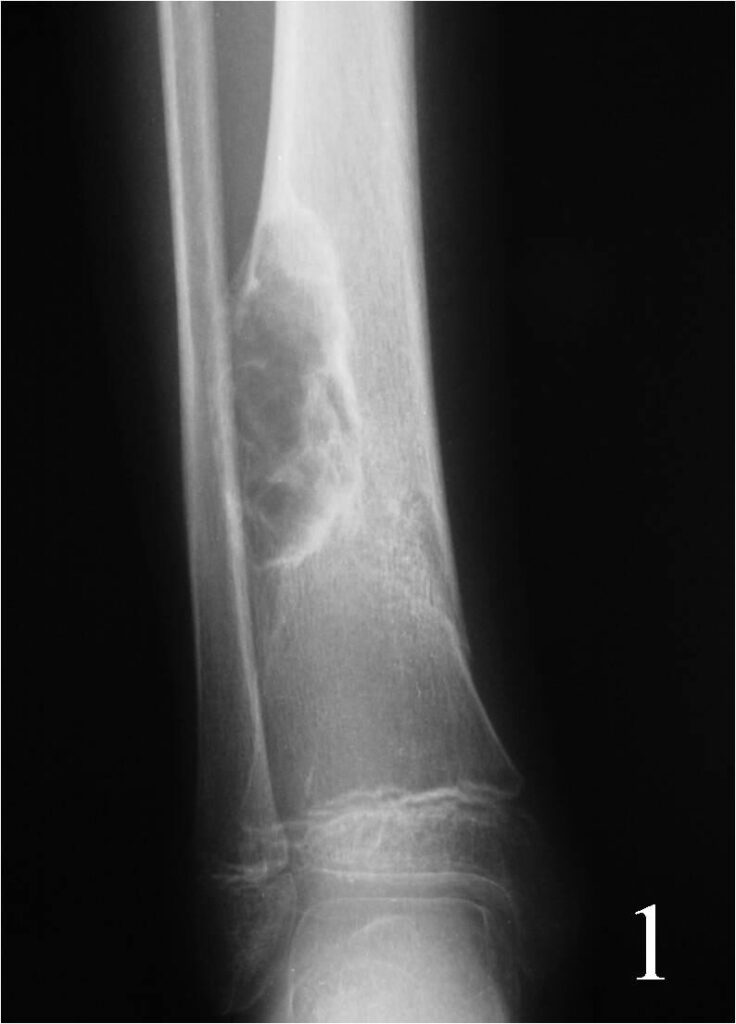

• Lytic and irregular; Well circumscribed lesion with surrounding sclerosis (fig 1-3).

• Lesions are metaphyseal and eccentric arising from or involving the cortex

• May appear expansile and sharply marginated with sclerotic rim

• The long axis of the lesion usually runs parallels to the affected bone

• Often has reactive internal trabeculations

Fig. 1

Fig. 1-2: AP (Fig. 1) and lat (Fig. 2) plain x-ray of the distal tibia-fibula shows a nonossifying fibroma of the distal tibia with a nondisplaced pathologic fracture. The lesion is geographic, well circumscribed, lytic, eccentric, arising in the metaphysis and has internal trabeculations. There is a sclerotic margin.